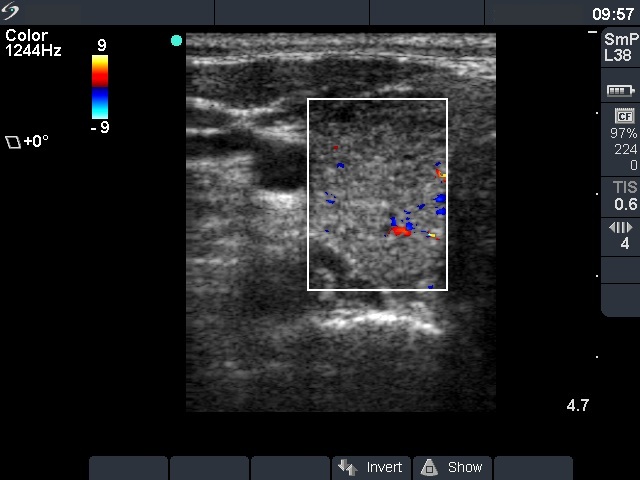

First examination - before surgery (1st row of images)

Clinical presentation: a 47-year-old woman was referred for evaluation of nodular goiter. She noticed a lump in the left lobe for a month.

Palpation: a large nodule in the left lobe.

Results of blood test: euthyroidism (TSH 3.31 mIU/L).

Ultrasonography: the right thyroid was echonormal and contained hypoechogenic areas. The left lobe was moderately hypoechogenic. There was a large hyperechogenic nodule in the left thyroid. The nodule displayed halo sign and type 2 vascular pattern.Cytology resulted in benign lesion.

Final diagnosis. Benign nodule in the left thyroid. Chronic lymphocytic thyroiditis. Left lobectomy was advised because of the size of the nodule.

Histopathology disclosed benign hyperplastic nodule and chronic lymphocytic thyroiditis.